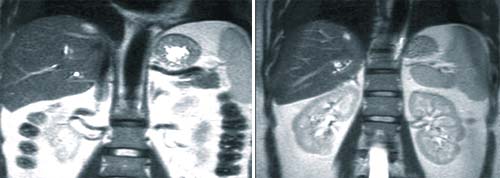

| |

Phì đại ống dẫn mật trong gan dê do F.hepatica | Sán trưởng thành F. hepatica tại đường mật dê |